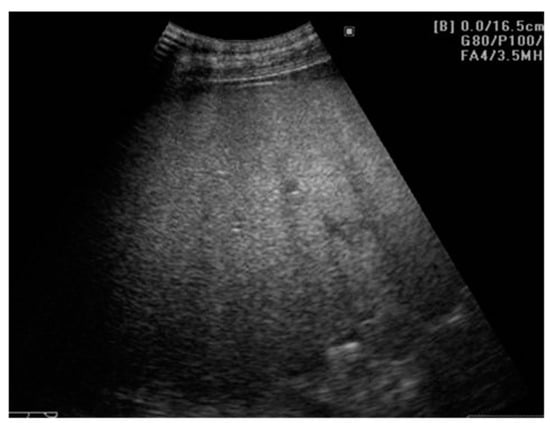

2.1. Evaluating NAFLD Using Conventional US

2.1.1. Ultrasound Diagnostic Criteria for Hepatic Steatosis

2.1.2. Quantitative Assessment of Hepatic Steatosis

2.1.3. US Performance for Steatosis Detection

2.1.4. Ultrasonographic Steatosis Patterns

2.1.5. Limitations of Ultrasonography in Steatosis Diagnosis